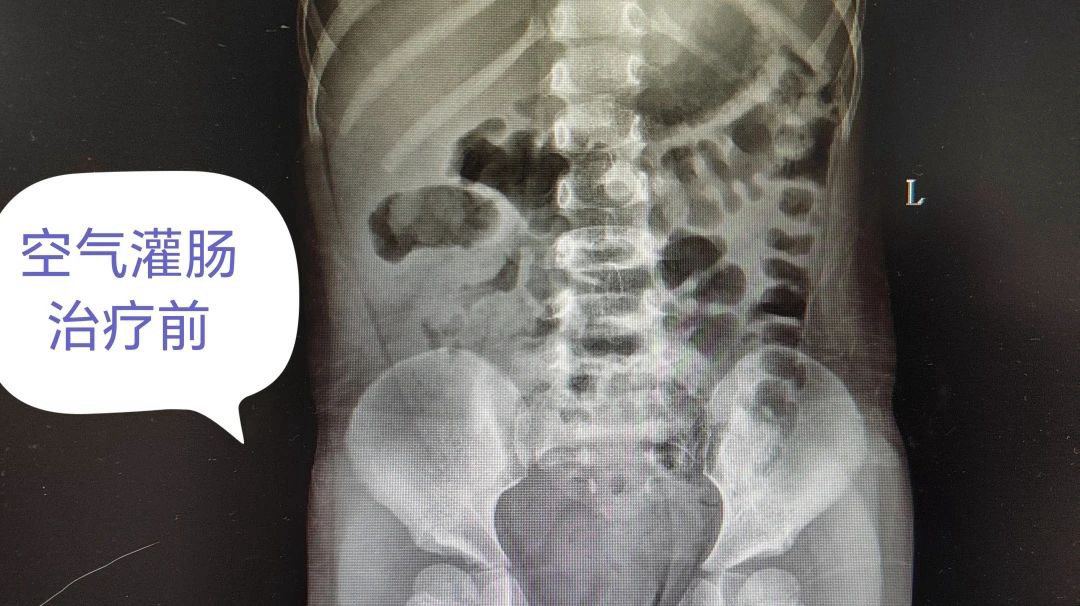

目前小儿肠套叠的治疗以非手术疗法为主,常用治疗方法有空气或者钡剂灌肠和水灌肠。其中空气灌肠效果最好,最安全!即在X线监视下,通过肛门向肠道内注入空气,在一定的压力下可以将套在一起的肠管冲开,将套入的肠管推出复位肠套叠。空气灌肠整复既是检查方法又是一种治疗手段。在X线下做空气灌肠整复治疗肠套叠无损伤、效果显著。

▲ 空气灌肠治疗前